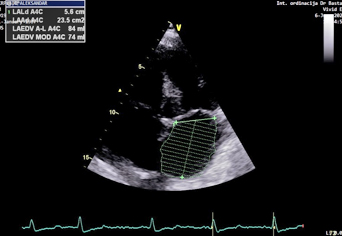

Leva pretkomora je dilatirana, indeks zapremine leve pretkomore

(LAVI) je 45 ml/m2 (normalno<34 ml/m2) (Slika 5). Izmerena je

Slika 5. indeks zapremine leve pretkomore(LAVi)